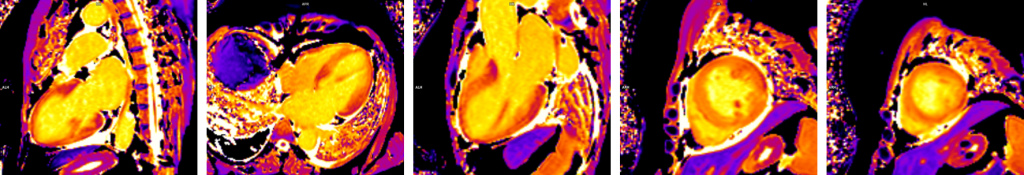

Figura 1: Achizitie harta T1 (T1 mapping) precontrast

Figura 2: Achizitie harta T2 (T2 mapping)

Figura 3: Achizitie harta T1 (T1 mapping) postcontrast